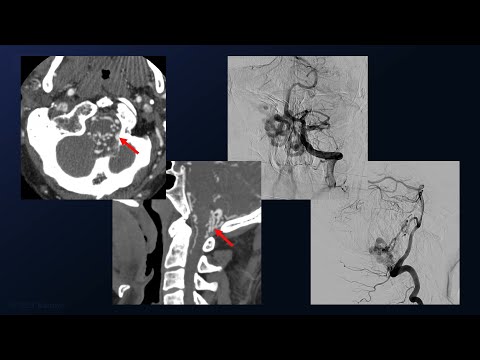

Spinal Dural AVF